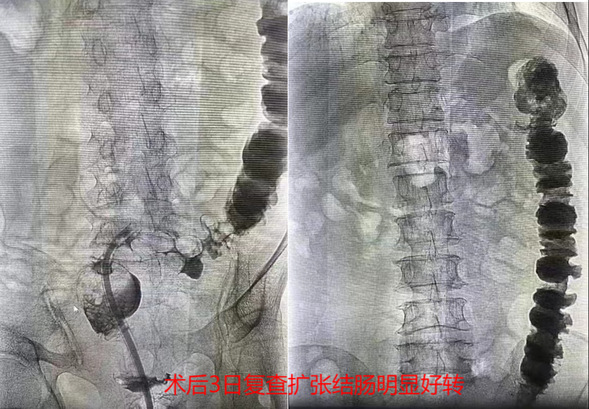

术后,在我院医护人员、患者及家属共同努力下,坚持经肠梗阻导管冲洗减压,患者腹胀腹痛症状较前明显好转。